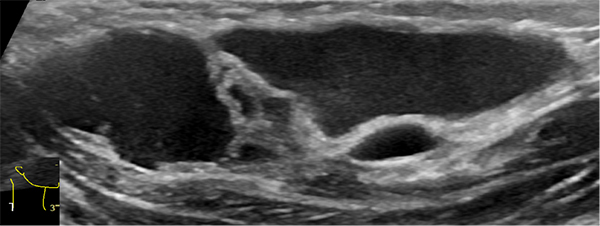

由于淋巴管畸形可发生在身体的任何部位,大多数发生在头颈部,其次为腋窝、纵膈及四肢。通常进行超声、磁共振、CT、诊断性抽液等检查,必要时依据情况进行穿刺活检,基本可以确诊。当怀疑患有淋巴管畸形时,应首先做超声检查,查清楚病变的部位、性质、大小及与周围组织的关系,评估是否需要治疗以及如何治疗。

淋巴管畸形超声:精准定位病灶部位范围以及与周边脏器的关系